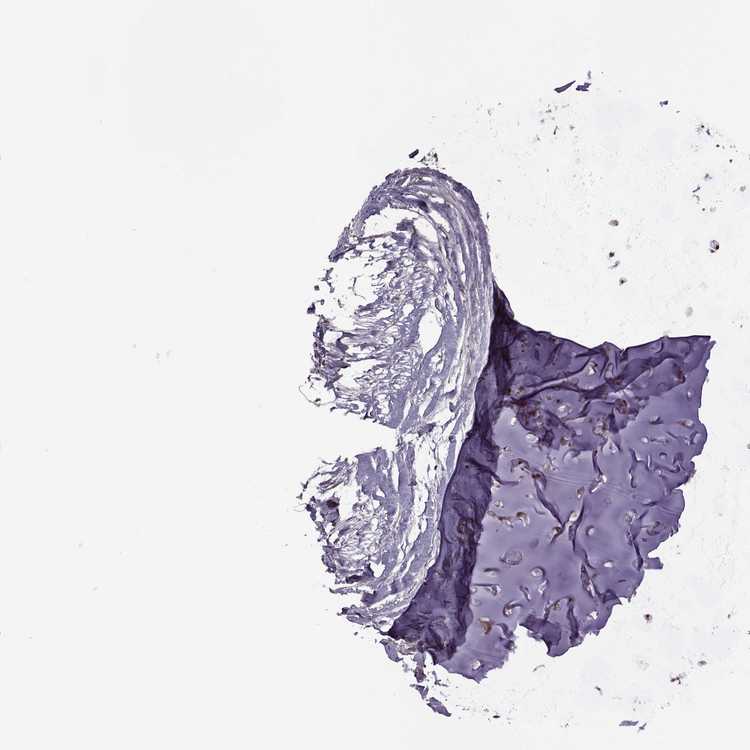

SOFT TISSUE 2 - Antibody stainingi

Antibody staining in the annotated cell types in the current human tissue is reported as not detected, low, medium, or high, based on conventional immunohistochemistry profiling in selected tissues. This score is based on the combination of the staining intensity and fraction of stained cells.

Each image is clickable and will lead to virtual microscopy that enables deeper exploration of all samples and also displays staining intensity scores, fraction scores and subcellular localization as well as patient and tissue information for each sample.

Antibody HPA075125

Fibroblasts Medium

Peripheral nerve Low